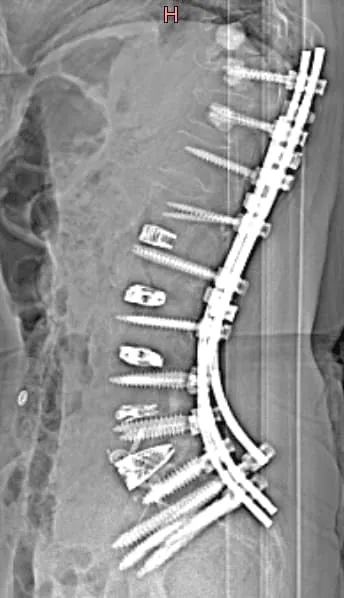

Fusion Frequently Needed

X-ray of a spine with surgical rods and screws implanted along the vertebrae.

90%+ Need Additional Surgery